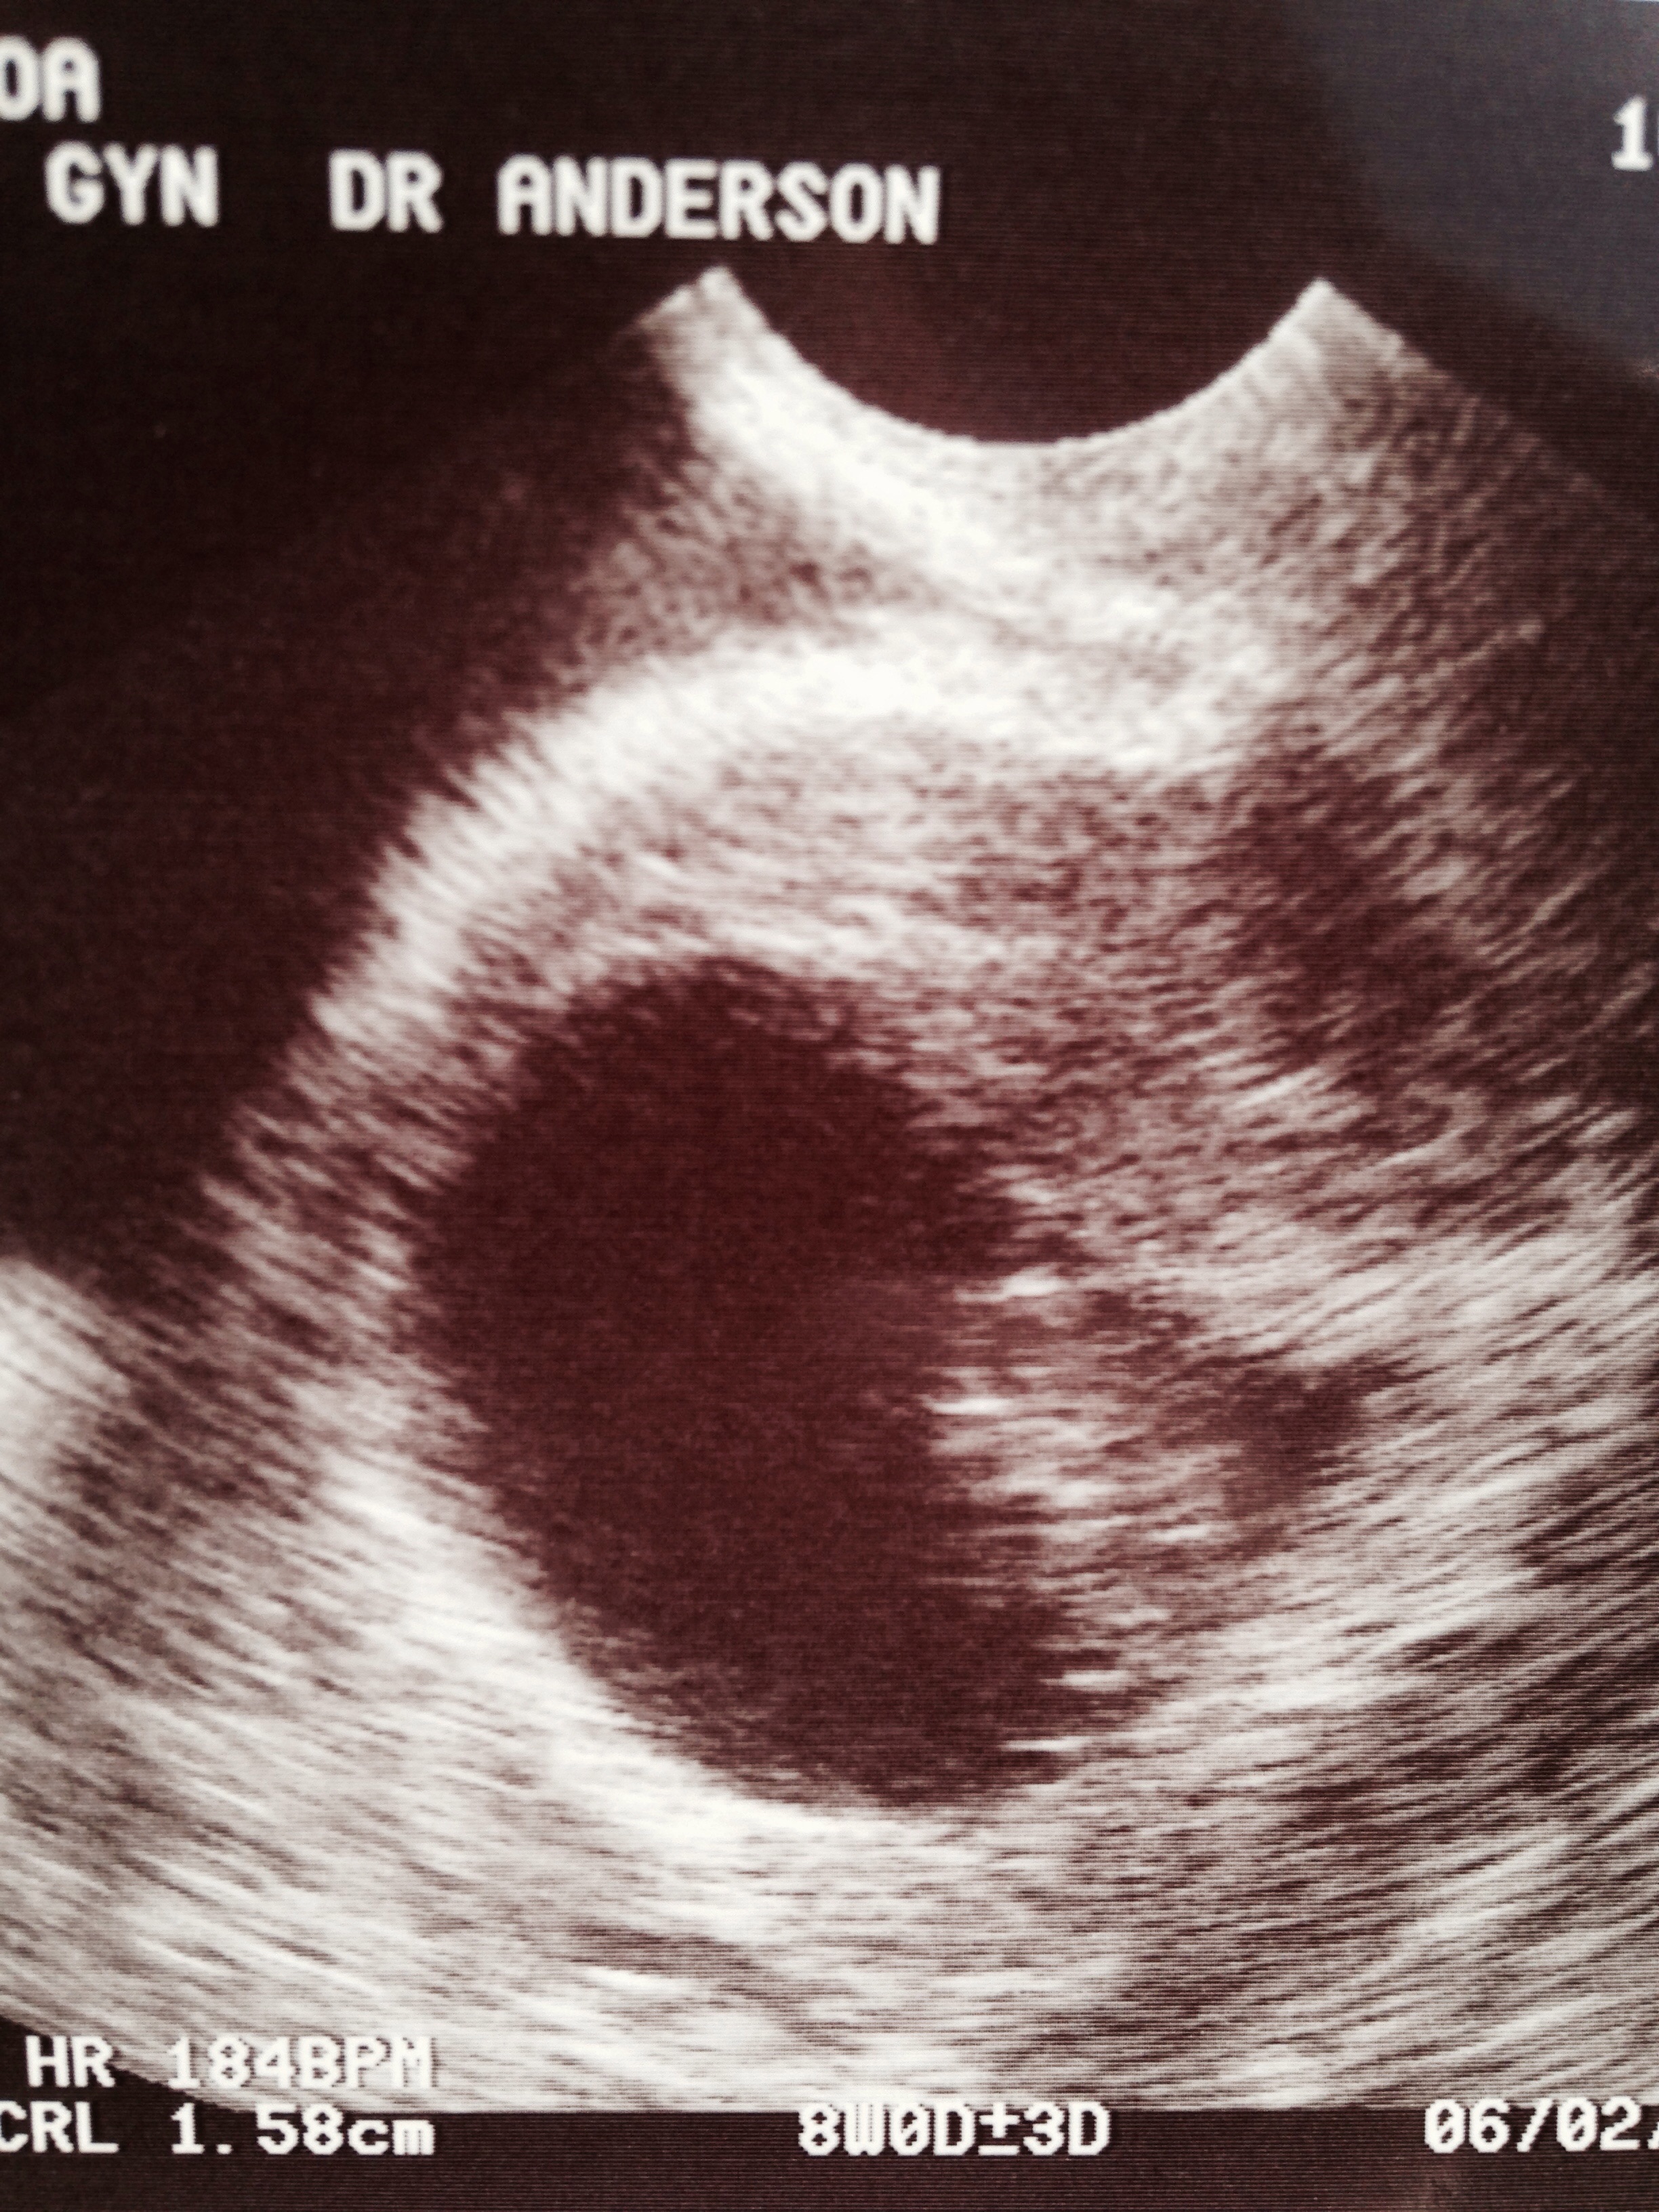

I had a missed miscarriage in June after seeing a low heart rate at 6 weeks. Waited this time to go in at 8 weeks according to my LMP, and was so happy to see a heart rate of 184 and actually measuring at 8 weeks. In June I thought I was six weeks when I went in but was only measuring five, and then went back a week later and the low heart rate, then back two weeks later and no heart rate and was measuring five weeks. So even though my ultrasound this time was awesome at 8 weeks I am still cautiously optimistic. Go back next Tuesday at 10 weeks and hoping the little one is measuring ten weeks. I feel more pregnant this time around than last. Last time just had a little fatigue and a metallic taste. This time having full blown fatigue, nausea, acne, and overall feel like crap. But so worth it for a happy healthy baby in June! Sorry for the long post : )